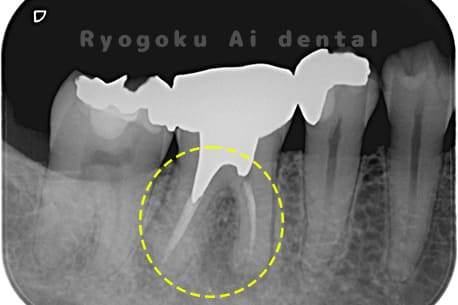

Case28

-

- 原因

- 慢性根尖性歯周炎

- 治療内容

- マイクロエンド治療

- 治療費用

- 121,000円

- 担当医

- Dr. 炭野

左下が噛むと痛いとのことでご来院された患者様です。マイクロエンド治療で行いました。

<リスク・副作用>

手術後は痛み、腫れ、痺れ、青あざなどの副作用が生じます。痛みは痛み止めを処方しますが、腫れ、青あざは1週間程度生じる場合があります。また、部位によっては神経の走行が複雑で、痺れが残り、長期的にお薬を処方する場合があります。